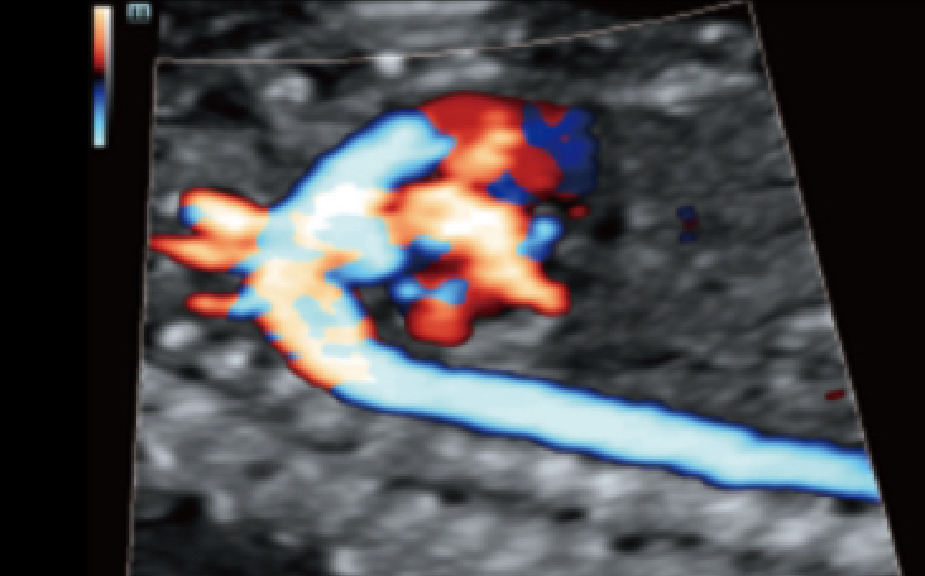

Smart Pelvic

En vistas de la creciente importancia del diagnĂłstico por ecografĂa en los trastornos del suelo pĂ©lvico, Smart Pelvic ofrece una nueva soluciĂłn para simplificar en gran medida los procedimientos y minimizar el tiempo de examen para una evaluaciĂłn estandarizada. Con una interacciĂłn con el usuario extremadamente simple, genera un sistema de coordenadas estĂĄndar y proporciona todas las mediciones relacionadas automĂĄticamente en unos pocos segundos.